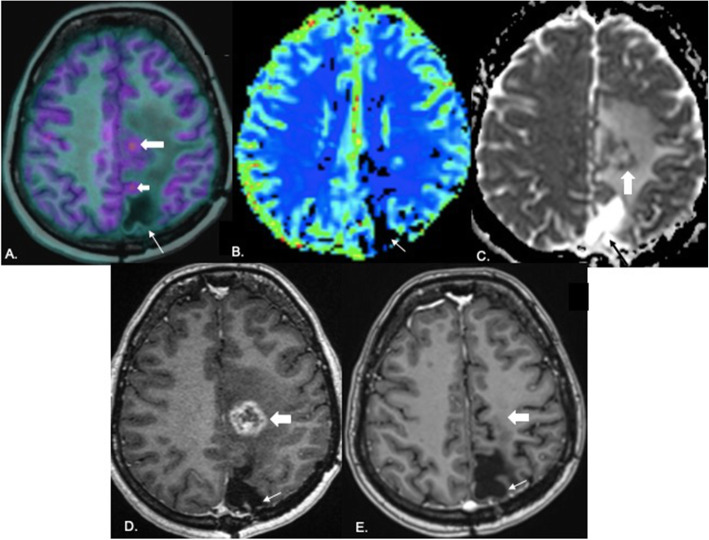

Fig. 5.

Concordant PET, perfusion, diffusion and enhancement in a case of recurrence: 40-year-old male diagnosed with anaplastic ODG 15 months back. Underwent surgical excision followed by radiotherapy completed 13 months earlier. PET image overlaid over T1 MPRAGE (A) shows a large area of uptake in the left temporoparietal region (white arrow). rCBV map (B) generated with the leakage correction algorithm shows elevated perfusion in the same region (white arrow) with diffusion restriction on the ADC map (white arrow in C). Note enhancement on the post-contrast image (white arrow in D). In view of unequivocal evidence of recurrence, surgery was planned. Post-contrast axial CT brain acquired prior to surgery (E) shows an enhancing left parietal lesion (white arrow). Post-operative plain axial CT brain (F) shows the resection cavity (white arrow) with gross total excision. Histopathology revealed recurrent GBM. This is a case of recurrence where the PET, perfusion, diffusion, and contrast images were concordant with good spatial congruence

Fig. 6.

Discordance between PET, perfusion and diffusion in a case of recurrence: 31-year-old male operated for right frontal ODG 14 months back; last radiation dose 10 months ago. PET images fused with axial T1 MPRAGE (A, B) show an area of uptake in the right superior frontal gyrus (white arrow in A, B). The uptake (block white arrow) is seen along the margins of the resection cavity (small white arrow) on the coronal fused PET-MR image (C). rCBV map (D) generated using the leakage correction algorithm shows no unequivocal elevation of perfusion in the area. There is no diffusion restriction on the ADC map (E). Few foci of enhancement (block white arrow) are seen along the margins of the resection cavity (small white arrow) on post-contrast coronal T1 MPRAGE (F). In view of PET uptake, recurrence was suspected and chemotherapy administered. Follow-up PET image after chemotherapy fused with coronal T1 MPRAGE (G) shows reduction in the degree of uptake (block white arrow) along the resection cavity margin when compared with prechemo coronal PET image in C. Reduction in the degree of enhancement is also seen on the follow-up post-contrast coronal T1 MPRAGE (white arrow in H) compared to that in F

Fig. 7.

False positive diagnosis on PET: 34-year-old female diagnosed with anaplastic ODG 2 years back with enhancing lesion on MRI. PET image fused with axial T1 MPRAGE (A) shows an area of uptake along the parasagittal region of the left frontal lobe (large thick arrow) and another area (small thick arrow) along the margin of the resection cavity (linear white arrow) raising a suspicion of recurrence. There is no evidence of elevated perfusion on the rCBV map (B). Resection cavity is shown by white arrow. Peripheral diffusion restriction is seen along the margins of the lesion in the left centrum semiovale (block white arrow in C). There is no restriction along the resection cavity (black arrow). Peripheral enhancement is seen along the margins of the lesion in the left centrum semiovale (block white arrow in D) with no enhancement along the resection cavity (white arrow). One month follow-up axial post-contrast T1 MPRAGE (E) shows the resection cavity (thin white arrow) with complete resolution of enhancement in the left centrum semiovale (block white arrow) suggestive of treatment related changes excluding recurrence